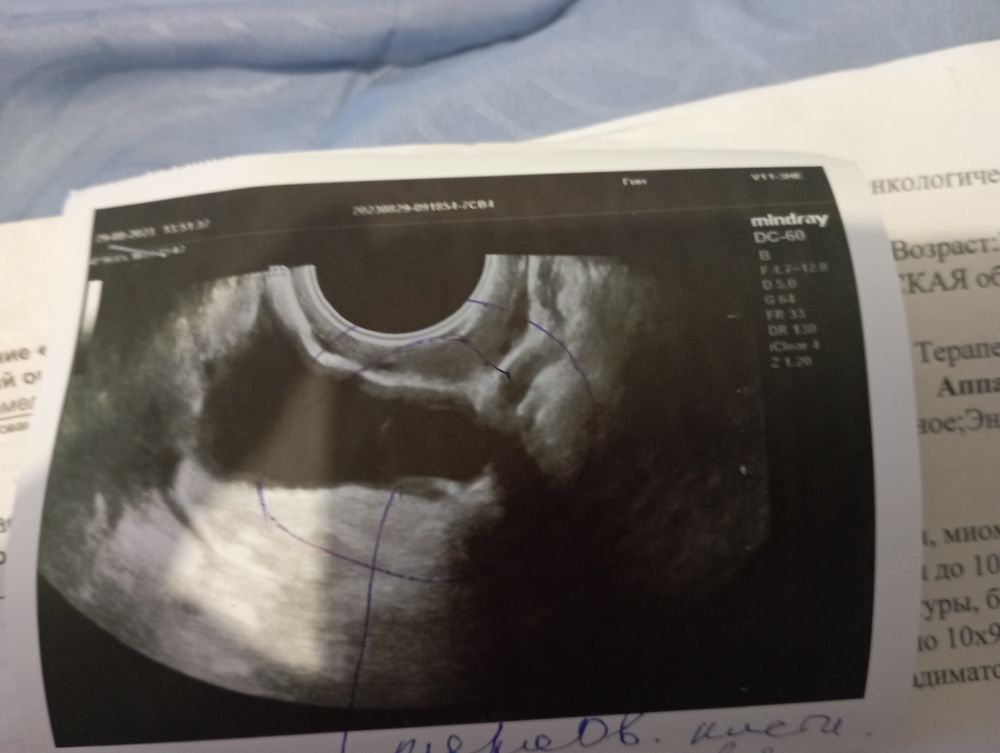

Узи малого таза

Miss Fisher, в заключении написано кисты на шейки матки еще есть

Юлия Цурий, не обратила внимания. Это тоже не страшно. Понаблюдают, если что то будет не нравиться - отправят удалять. Вы, главное, не пускайте на самотёк, проверяйтесь так часто, как врач скажет.